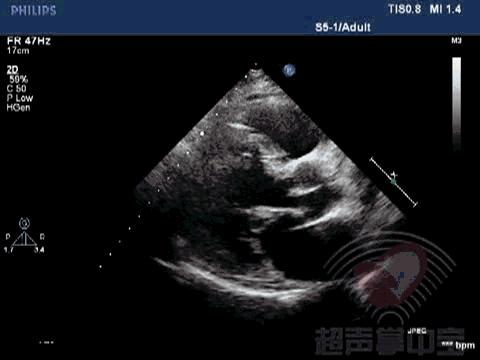

经典病例▏二尖瓣囊肿中竟然全是血液? 图1:心尖四腔心切面显示二尖瓣前叶增厚,前叶左房面可见一囊袋状物附着,大小2.01×2.17cm,囊壁完整,其内透声良好

经典病例▏二尖瓣囊肿中竟然全是血液? 动态图2:四腔心切面显示该囊状物质软,有形变,二尖瓣开放正常

经典病例▏二尖瓣囊肿中竟然全是血液? 动态图3:左室长轴切面观察该囊状物质软,有形变,随二尖瓣运动而摆动

经典病例▏二尖瓣囊肿中竟然全是血液? 动态图4:心尖左室长轴切面观察该囊状物质软,有形变,随二尖瓣运动而摆动

经典病例▏二尖瓣囊肿中竟然全是血液? 动态图5:心尖两腔心切面观察囊肿物

超声成像可以显示血液充盈性囊肿形态学及内部回声的特征,包括很薄的囊壁、其内充满无回声的血液,收缩期呈充盈状态圆形,舒张期可发生形变等。借助彩色多普勒及超声造影,可以显示囊肿内部血流与心室内血流相互沟通,从而进一步诊断血液充盈性囊肿。